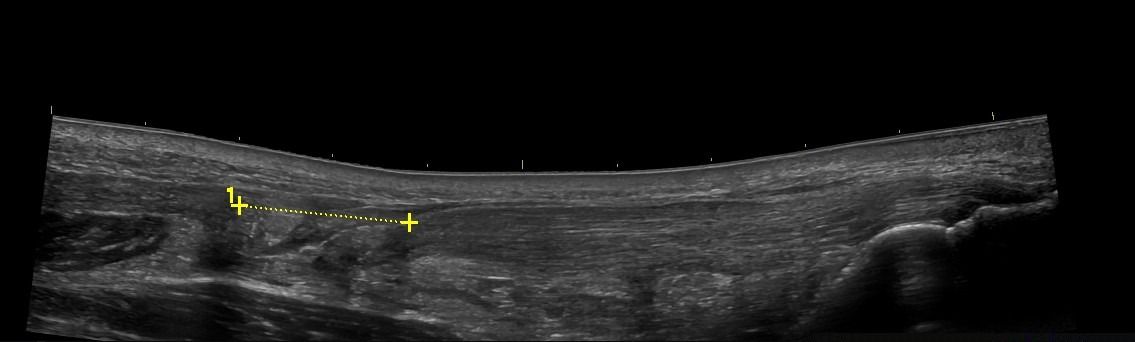

- Plantar Fasciitis

- Plantar Fibromatosis